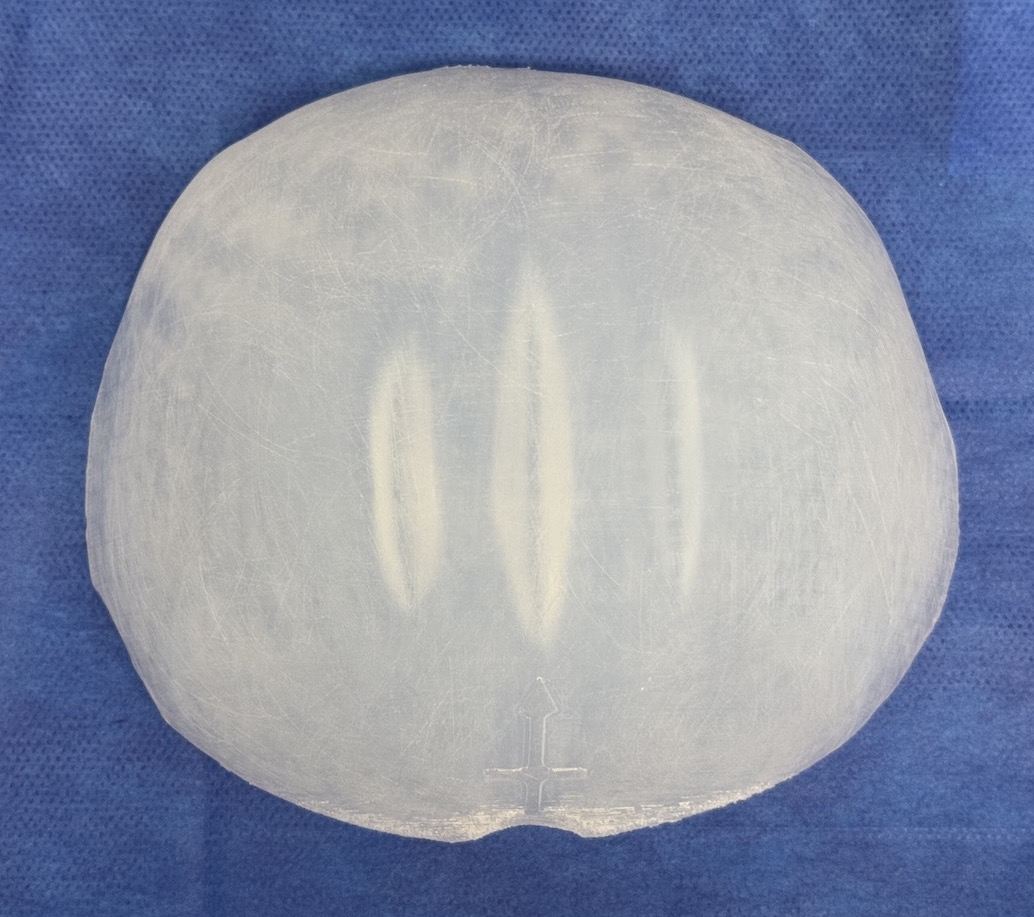

Desire for large overall skull augmentation procedure. Two piece custom skull implant designed with 250ccs volume.

1st stage scalp expander placed and inflated to 225ccs. 2nd stage two piece skull implant placed 4 months later.

Desire for large overall skull augmentation procedure. Two piece custom skull implant designed with 250ccs volume.

1st stage scalp expander placed and inflated to 225ccs. 2nd stage two piece skull implant placed 4 months later.